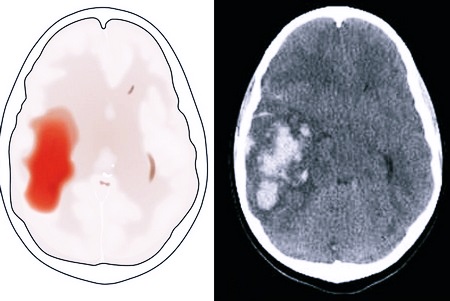

- Компьютерная томография.

Диагностика

Чтобы поставить диагноз, пациента опрашивают, выслушивают все его жалобы, изучают анамнез. Обязательно должен быть проведен осмотр неврологом. Всего этого вполне хватает, чтобы предположить наличие проблем с кровообращением в мозговых структурах. Для подтверждения диагноза, установления геморрагического характера патологии, проводится несколько обследований: